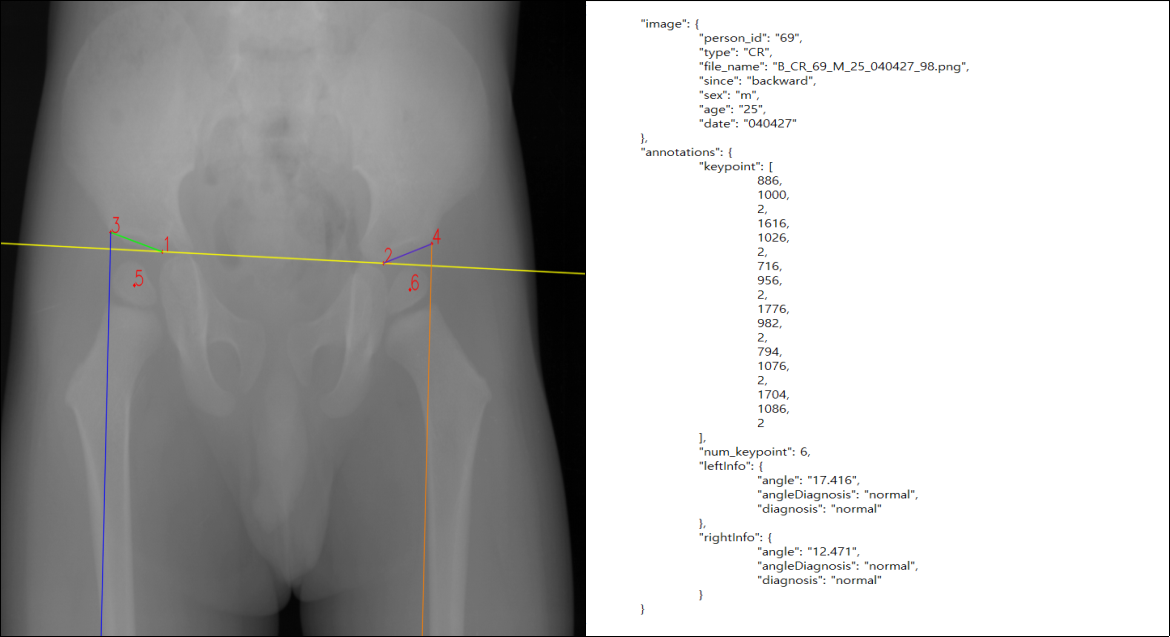

2. 라벨링 데이터 구조(X-ray)

| X-Ray | |

4. 어노테이션 포맷(X-ray)

| 항목명 | 타입 | 필수여부 | 설명 | 범위 |

|---|---|---|---|---|

| image | object | |||

| person_id | number | Y | 비식별화된 환자 id | |

| type | string | Y | x-ray | CR |

| file_name | string | Y | 파일 이름 | |

| since | string | Y | 전/후향적 | “backward”, “forward” |

| sex | string | Y | 성별 | “m”,“f” |

| age | number | Y | 월령 | 0~66 |

| date | string | Y | 검사일자 | yymmdd |

| annotations | object | |||

| keypoint | array | Y | 키포인트 좌표들 | |

| num_keypoint | number | Y | 키포인트 개수 | 6 |

| leftInfo | object | 왼쪽 정보 | ||

| angle | number | Y | 각도 | 0~90 |

| angleDiagnosis | string | Y | 각도로 판단된 질환 | normal, “dysplasia” |

| diagnosis | string | Y | 질환 | normal, “abnormal” |

| rightInfo | object | 오른쪽 정보 | ||